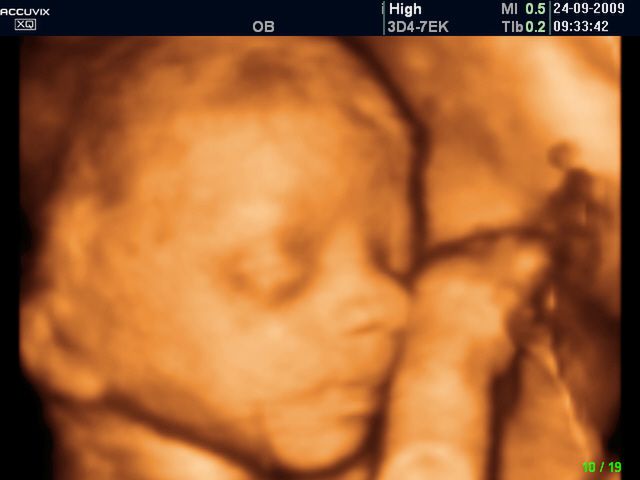

/ 5Płód w 26 tygodniu ciąży - twarz dziecka

W 26 tygodniu oczy dziecka otwierają się